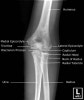

2. Elbow AP view

- Elbow Oblique view

- Elbow Ossification Centres

A useful mnemonic for remembering the order of the ossification centres is the CRITOL rule

Capitellum

Radial head

Internal (medial epicondyle)

Trochlea

Olecranon

Lateral epicondyle

It is noteworthy that the ossification centres of the elbow do not always follow this order of ossification.